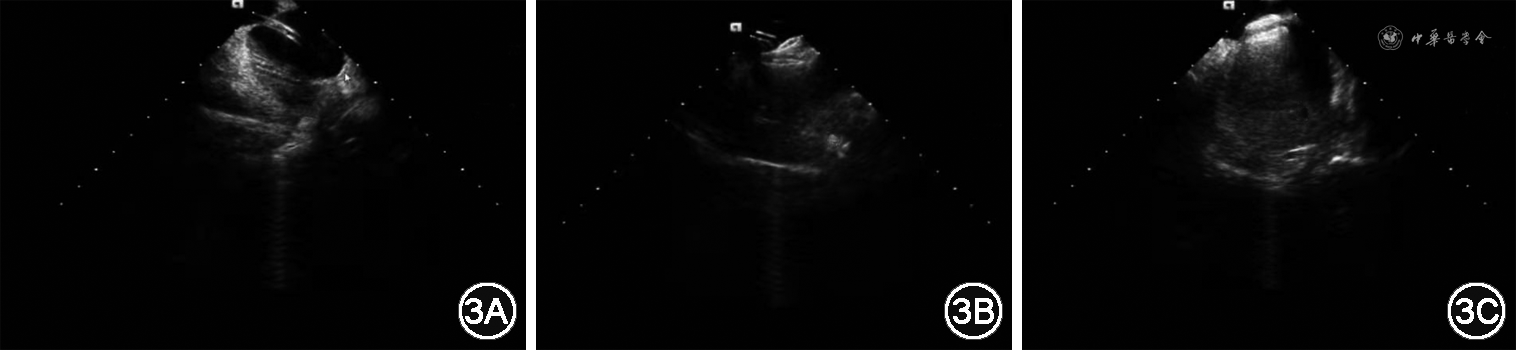

2020年3月8日在局麻下行心腔内超声(ICE)指导房间隔穿刺PFO封堵术。采用强生Cartosound心腔内超声导管,直径10 Fr(3.2 mm),工作长度90 cm,操作手柄具有强力微调技术,保持弯度,前(A)、后(P)、左(L)、右(R)四向160°打弯,从任意角度观察心脏内解剖结构及位置,相控阵超声探头频率4.5~11.0 MHz,将Cartosound导管通过Swifilink连接装置与西门子SC2000彩色多普勒超声诊断仪相连。穿刺右侧股静脉,置入11 F鞘管,ICE导管经右侧股静脉穿刺插管送入右心房,分别进行二维、彩色多普勒血流显像和连续多普勒检查,观察PFO的解剖形态、周边结构以及血流力学,并在二维图像上测量基础状态PFO通道的直径和长度。常规消毒、局部麻醉后穿刺右股静脉,送入动脉鞘管,将带有引导钢丝的房间隔穿刺鞘管经右股静脉穿刺送入上腔静脉,沿上腔静脉下滑至卵圆窝处,ICE导管显示“起始扇面”,顺时针旋转至左肺静脉扇面,打“P”弯至主动脉根部出现,打“R”弯显示上腔静脉,同时展示卵圆孔的整体形态,调整房间隔穿刺鞘管,并可看到“帐篷顶”。突破房间隔后,注射生理盐水左心房内可见气泡显影,确认穿刺成功。将端孔导管通过PFO经左心房送至左上肺静脉,导入0.035英寸(1英寸=2.54 cm)260 cm长加硬钢丝,送入输送鞘管(图3A),选择合适的PFO封堵器并安装至输送杆上,在ICE引导下穿过PFO进入左心房,并确保钢丝位于左上肺静脉内,将封堵器沿输送鞘管送至左心房,依次释放左心房盘面、腰部及右心房盘面(图3B),ICE实时观察封堵器形状及位置均良好(图3C),超声造影证实封堵效果满意(无RLS,二、三尖瓣未受累等),心电图监测无传导阻滞,释放封堵器。手术成功,术后给予抗血小板、抗凝治疗。术后3个月随访,复查TTE显示封堵伞位置良好,右心声学造影未见RLS。